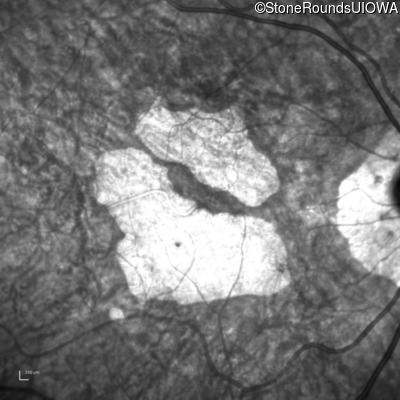

Infrared Fundus Photograph - Left - 20/40 +2

Exemplar